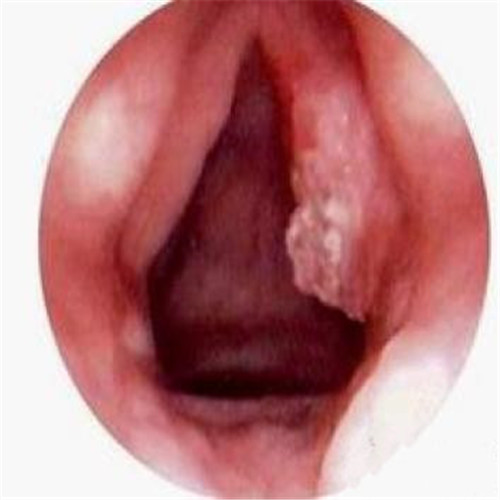

呼吸道感染者扁桃體發炎切除物